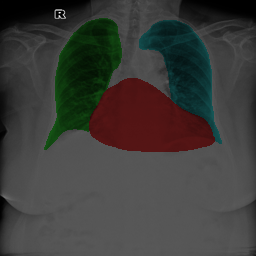

To bridge the methodological gaps when only small-scale partially labeled data is available, we propose a simple yet efficient framework Vicinal Labels Under Uncertainty (VLUU) by exploring the statistical similarity of human structures (e.g. shape, size, location) among different patients. See Fig. 1 for an illustration of such a similarity. The proposed framework is motivated by vicinal risk minimization (VRM) [11], where the fully labeled vicinal examples are generated by linearly combining randomly sampled partial labels with a weight randomly sampled from a Dirichlet distribution. These vicinal examples allow us to transform the partially supervised problem into a fully supervised one. That is to say, we can utilize any existing supervised segmentation networks and loss functions to solve partially supervised problems. The generated vicinal labels contain uncertainty regions where classes of interest could potentially overlap. We utilize these uncertainties in the training process to improve the robustness of DL models.

In standard adversarial training, the segmentation network and the discriminator play a zero-sum game. The discriminator is trained to discriminate the prediction masks produced by the segmentation network from the ground truth masks. Meanwhile, the segmentation network is trained to confuse the discriminator by producing realistic prediction masks. Adversarial training benefits from the human structure similarity as it makes the unknown true label distributions easier to be caught by the discriminator than for general objects [38]. In other words, there is smaller instance-wise variation in the size, shape, and location of human organs (or structures), as shown in Fig. 1, than for general objects.